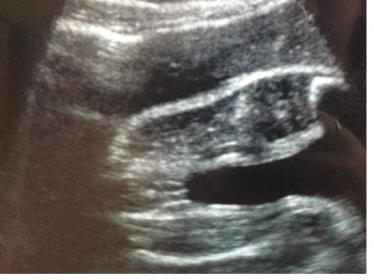

Hi can someone help me what they think the sex of baby is - I thought girl from the "three lines" one but the other one is throwing me because it looks protruding... they are both from the same scan but my area dont tell you sex of the baby so frustrating!!!

Attachment 38992Attachment 38993